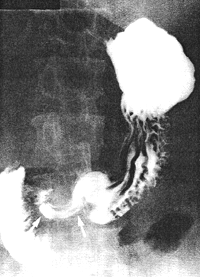

Attempts at controlling the diabetes in a peripheral hospital were only partially successful. She was readmitted 14 months later in a disorientated state with uncontrolled diabetes mellitus, diffuse abdominal pain and diarrhoea. Abdominal sonography was normal. Upper gastrointestinal radiological examination after an overnight fast showed numerous food residues in the stomach. Gastric peristalsis was decreased as before. The pyloric sphincteric cylinder remained partially contracted with absent cyclical activity, and contained food residues and unidentified tablets which she had found in the ward and swallowed the previous day (Fig. 37.2). (Each tablet measured 1.1 cm in diameter on the films; owing to magnification the true diameter would be in the region of 8.0 to 9.0 mm). The pyloric aperture remained patulous and no obstructing lesion was seen. The condition was diagnosed as diabetic gastroparesis.

| Fig. 37.2. Case T.M. Absent cyclical activity of pyloric sphincteric cylinder. Pyloric aperture patulous. Retention of food residues and 8.0mm diameter tablets |